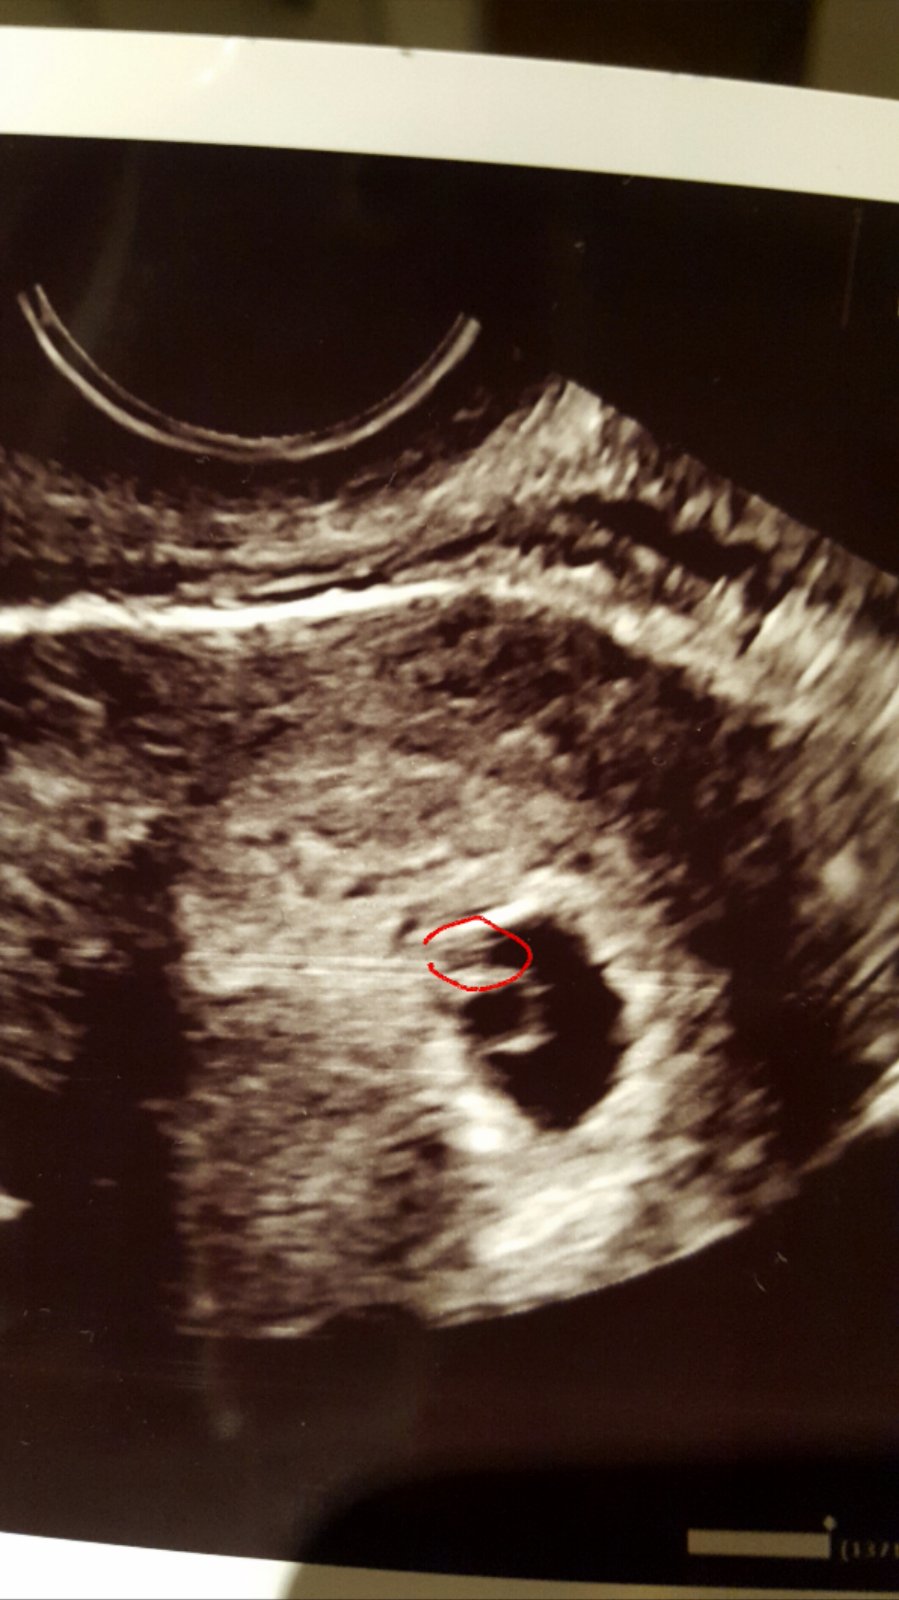

@emakiki Ja som mala hCG uz cez 2000 a peknu bublinku v brusku :( len hCG rastlo straaasne pomaly, az sa zastavilo. Tuto na utz mala mat bublinka 6+2tt, bohuzial merala iba 5+3tt